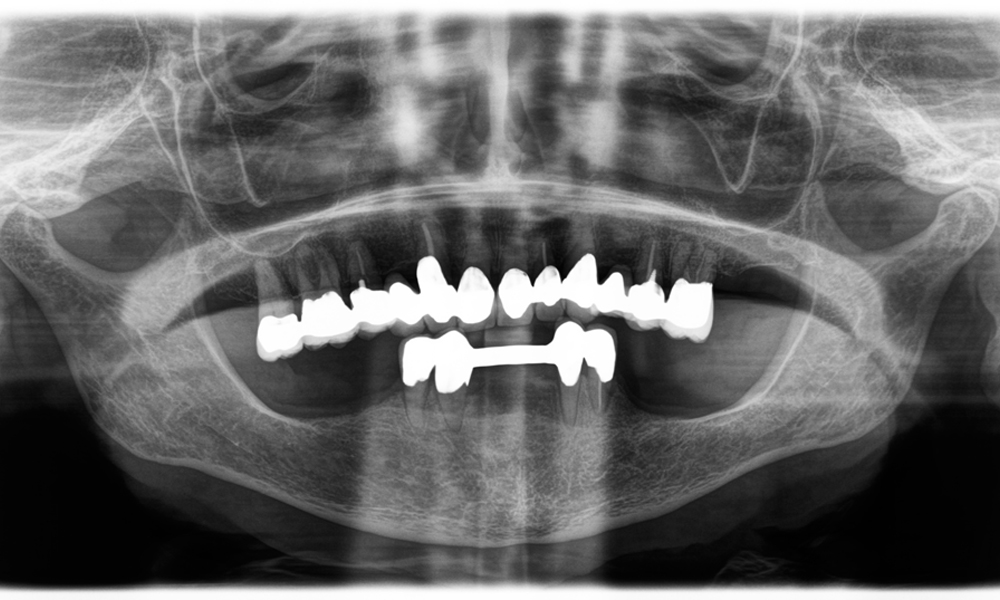

Dr. Wolfgang Tautschnig, ein erfahrener Zahnarzt aus Salzburg, hat die Synea Power Edition über mehrere Monate hinweg in seiner Praxis in verschiedenen klinischen Szenarien eingesetzt und evaluiert. Darunter vor allem für das Entfernen von Zirkonkronen und das Bearbeiten von unedlen Legierungen. In einem konkreten Fall stellte sich eine 81-jährige Patientin mit dem Wunsch nach einer ästhetischen Verbesserung ihrer 40 Jahre alten VMK-Kronen vor. Die bestehenden Kronen entsprachen nicht mehr den ästhetischen Ansprüchen der Patientin. Die Herausforderung lag in der Entfernung von zwölf verblockten Kronen mit unedler Legierung, ohne die darunterliegenden Zahnstümpfe zu beschädigen. Das Winkelstück wurde genutzt, um die Keramikschichten präzise einzuschlitzen sowie die Metallgerüste mit einem Hartmetallfräser zu trennen, um so die Kronen mit minimalem Trauma zu entfernen. Innerhalb von nur 30 Minuten waren die alten Kronen entfernt, danach konnte die neue Arbeit, bestehend aus Vollzirkon im Seitenzahnbereich und verblendeten Kronen im Frontzahnbereich, vorbereitet werden. Das Ergebnis war eine vollständige Neuanfertigung, die sowohl funktional als auch ästhetisch überzeugte (siehe Abb. 1).

Ein Kiefer-Röntgenbild einer 81-jährigen Patientin vor schwarzem Hintergrund.

Abbildung 1: Ästhetische Rehabilitation von VMK-Kronen: Vollständige Entfernung und Ersatz von 40 Jahre alten VMK-Kronen zur ästhetischen Verbesserung bei einer 81-jährigen Patientin.